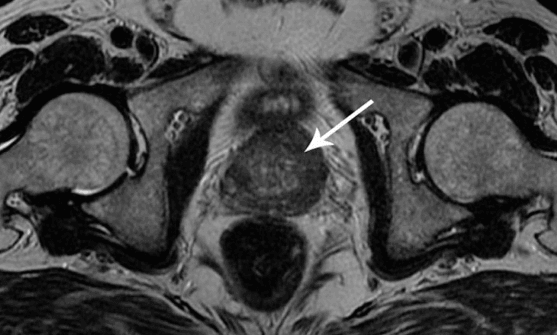

Voglio mostrarvi alcune foto per dimostrare cosa succede nel sistema urogenitale e in altri organi di un uomo che non fa sesso.

interesting image

Nelle foto vediamo l'infiammazione della prostata causata dal ristagno dello sperma (quando i testicoli non vengono svuotati). L'infiammazione persistente porta prima all'adenoma prostatico e successivamente al cancro. È la conseguenza inevitabile della prostatite, ed è per questo che viene chiamata la "malattia degli uomini anziani".